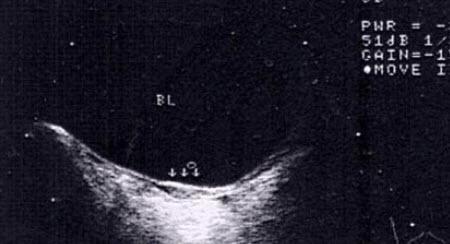

始基子宫,又称痕迹子宫。始基子宫属先天性生殖器发育异常,因两侧副中肾管汇合后不久即停止发育所致,常合并无阴道,但可有正常的输卵管与卵巢。这种子宫极小,仅1~3厘米长,大部分患者无宫腔、无子宫内膜,无月经来潮,且几乎都合并无阴道或仅有2-4cm深的阴道浅窝。阴道四维彩超,可以清晰地看到始基子宫的影像,始基子宫很小,似一条索状,无宫腔。发病率在1/4500,其中无阴道合并始基子宫占80%。肛诊时在相当于子宫颈、子宫体部位,触不到子宫而只扪到腹膜褶。